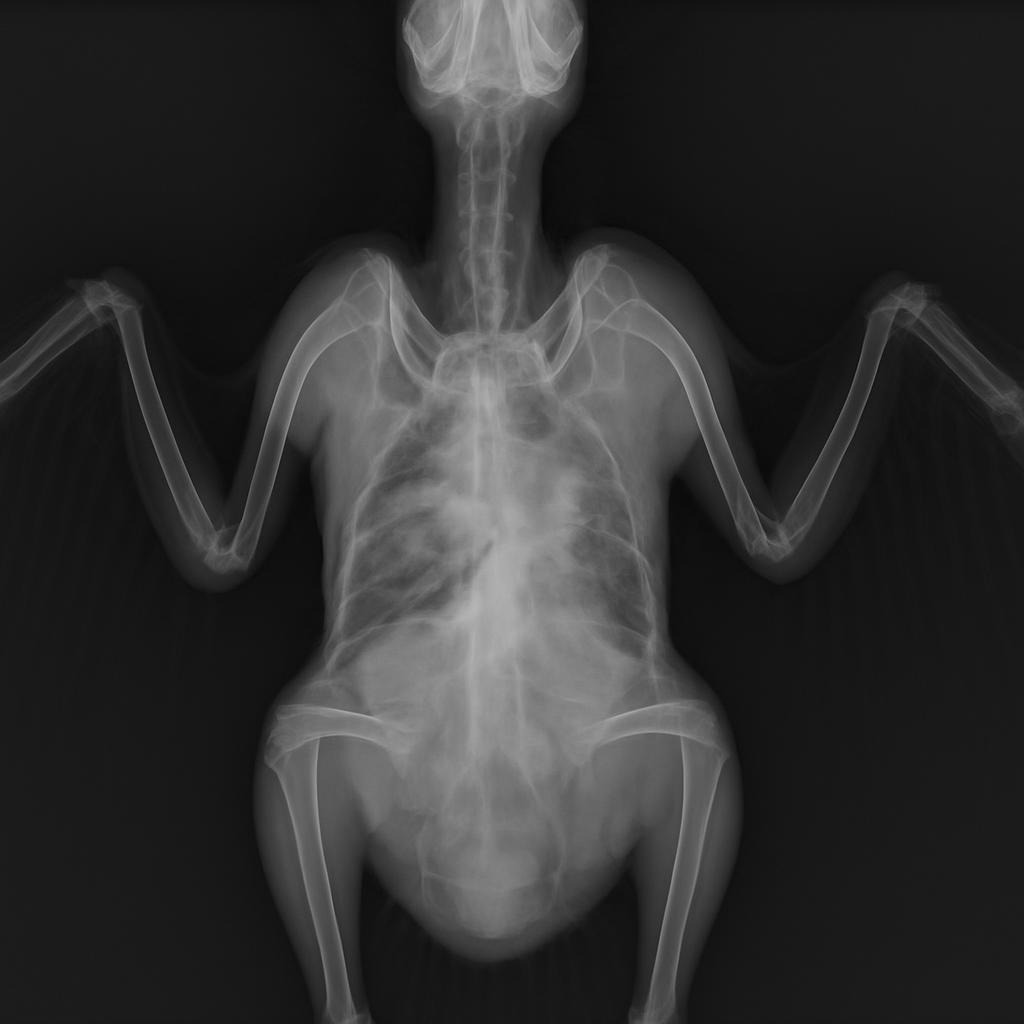

- Estrutura óssea: ossos fortes, densos, integridade do esqueleto para voo, preensão, locomoção.

O cálcio e o fósforo são minerais que atuam juntos em quase todos os processos vitais do organismo das aves. Aproximadamente 99% do cálcio e 85% do fósforo do corpo estão presentes nos ossos, formando cristais de hidroxiapatita — a estrutura que dá rigidez e resistência ao esqueleto.

Para que esses cristais se formem corretamente, é essencial que haja um equilíbrio adequado entre cálcio e fósforo na dieta. Se houver excesso de fósforo em relação ao cálcio, o organismo ativa mecanismos hormonais que retiram cálcio dos ossos para manter o cálcio sanguíneo estável, enfraquecendo a matriz óssea. Por outro lado, se o cálcio estiver muito acima do fósforo, a absorção de ambos os minerais pode ser prejudicada, resultando em depósitos de cálcio em tecidos moles ou em desequilíbrios metabólicos.

- Ossos frágeis, deformidades, problemas de crescimento, postura anômala.

- Em casos mais crônicos: osteoporose, redução na mobilidade, problemas de locomoção.